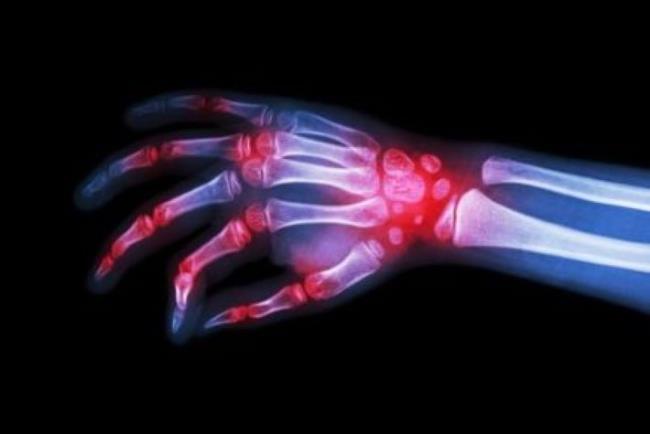

הידרוקסיכלורוקווין ניתנת במקור למניעה וטיפול במלריה, אך היא לא פועלת כנגד כל סוגי המלריה. כמו כן היא ניתנת, בדרך כלל בשילוב עם תרופות נוספות, לטיפול במספר מחלות אוטואימוניות, כגון לופוס (זאבת אדמנתית) ודלקת פרקים שגרונית. הטיפול במחלות אלו ניתן בדרך כלל כטיפול בקו שני לאחר שתרופות הקו הראשון אינן מצליחות לטפל בבעיה.

בחולי לופוס הידרוקסיכלורוקווין יעילה כנגד גילויי העור וכנגד דלקות המפרקים.